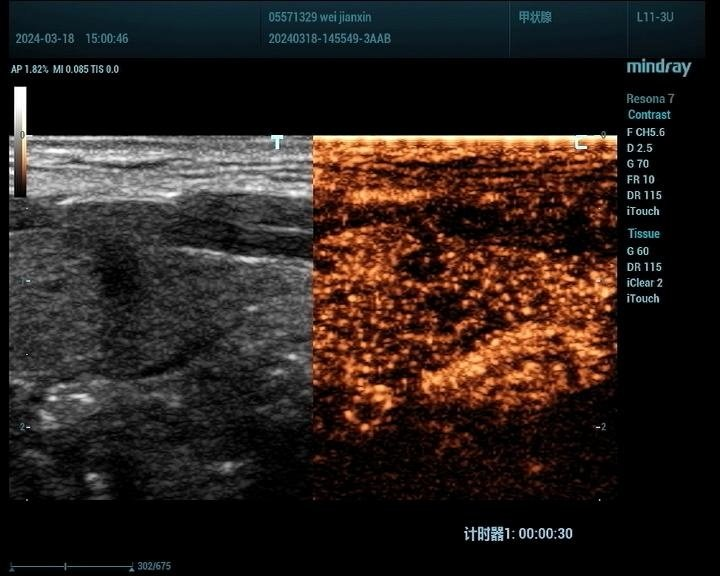

1、甲状腺:

观察甲状腺结节的血供情况:超声造影能够显示甲状腺结节的血供情况,有助于判断结节的活性及是否存在恶变倾向。

鉴别甲状腺结节的良恶性:通过超声造影,可以观察到结节的边界、形态、内部回声等特征,从而对结节的良恶性进行初步鉴别。

甲状腺癌病例